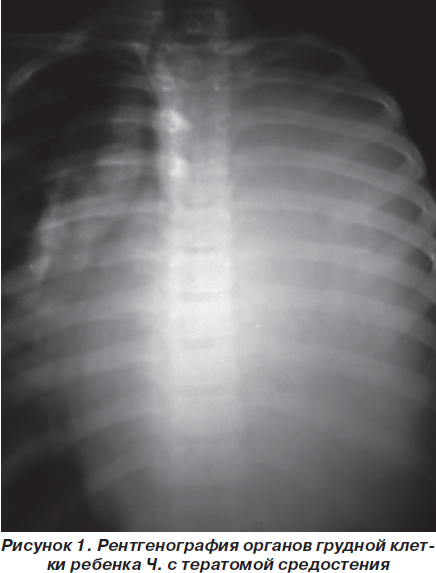

Рентгеновские снимки тератомы средостения: Диагностика и лечение

Раздел: Фотоэссе